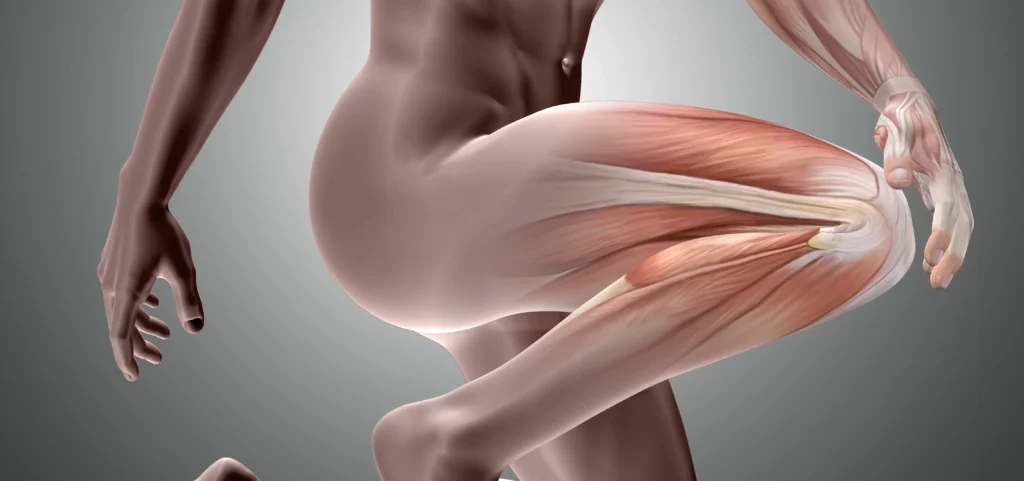

Bacaktan Vuran Ağrı: Siyatik Sinir Sıkışması

Bacaktan Vuran Ağrı: Siyatik Sinir Sıkışması